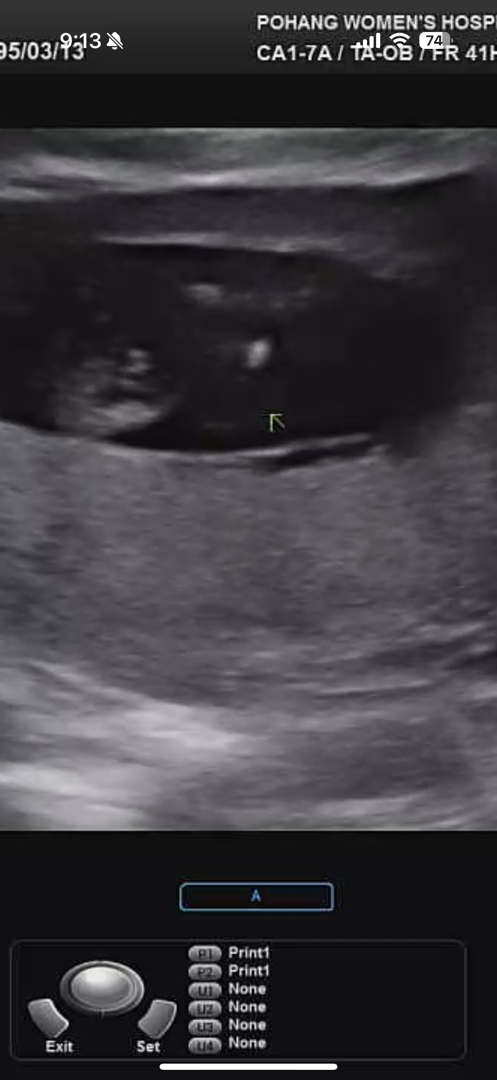

12주0일 초음파 사진인데 혹시 고수님들 보시면 알수있을까요??ㅠㅠ 제눈엔 죠리퐁이...보이는데... 아들이면 하는바램이라서요ㅠㅠ 반전잇을까요ㅠ 댓글에 다른사진도 있어요ㅠㅠ

다른사진은 이래요ㅠ